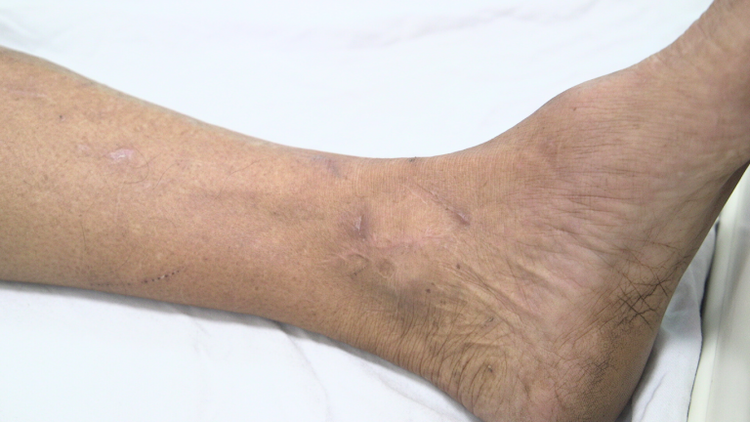

Bệnh nhân bị uốn ván bị nhiều vết thương ở chân - Ảnh BVCC

Qua khai thác bệnh sử, gia đình cho biết công việc hằng ngày của ông T. là phụ việc tại xưởng cơ khí. Trong quá trình vận chuyển vật liệu, ông thường xuyên bị va quẹt chân vào những thanh sắt tại nơi công trường, gây trầy xước nhiều vết thương nhỏ. Vết thương xảy ra 3 – 4 ngày trước đó, không được xử lý y tế đúng cách. Đặc biệt, ông T. chưa từng tiêm vắc xin phòng uốn ván trong đời.